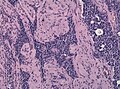

Microscopic

Features:[17]

- Loss of fibrous stroma.

- The cells of a normal (anterior) pituitary are nested.

- Basophilic cells (corticotrophs).

- Eosinophilic cells(somatotrophs).

- Extensive fibrosis often seen in TSH-producing tumors.

- Nonfunctioning pituitary adenoma (1).jpg

Pituitary adenoma - non-functioning. (WC/KGH)